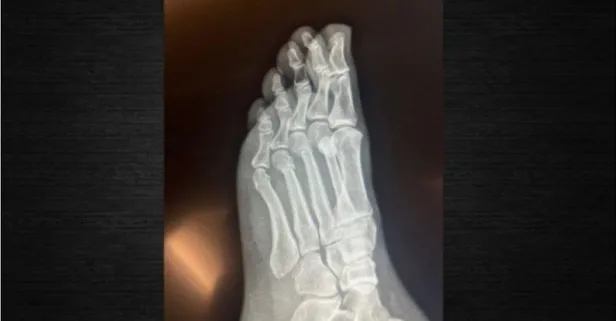

Ankara'da evinin merdiveninden düşerek ayağını kıran CHP Genel Başkanı Özgür Özel, kazanın ardından sosyal medyada yayılan, "ayağından vuruldu", "alkollüyken düştü" gibi iddialara yönelik açıklama yaptı. Röntgen filmlerini paylaşan Özel, iddialara ilişkin olarak "FETÖ'cü hesapların yaydığı bir yalan, daha sonra üzerine eklenerek, boyutlandırılarak kasıtlı olarak devam ettirildi" ifadesini kullandı. Bu iddialara yönelik, "Gelsinler röntgeni inceleyelim" diyerek bu kampanyanın "ahlak dışı olduğunu" açıkladı.